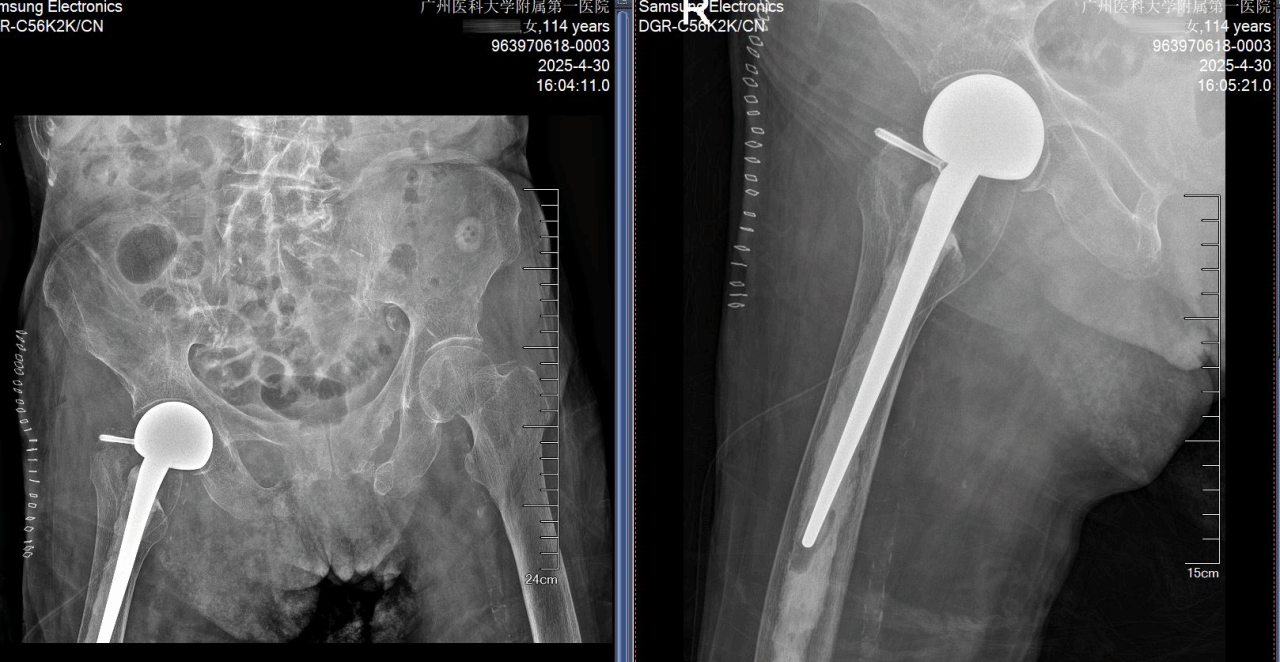

手术在卢伟杰主任医师的带领下稳步进行,手术团队配合默契、采用骨水泥固定技术,减少出血量、便于患者早期下地行走,在顺利完成关节置换的同时,极大降低手术创伤对病人的影响。由于准备充分,对患者全身情况干扰较少,手术结束后,患者直接返回普通病房,继续康复治疗。

患者术后72小时即实现行走突破,已能在助行器的帮助下行走活动,生活质量得到了显著改善。“她的毅力,连年轻人都自愧不如。”宋丽娟护士长感慨道。这场与时间的赛跑、与生命的较量,是医疗技术的胜利,也是精细化护理与人文关怀的完美结合。

术前术后X光照片